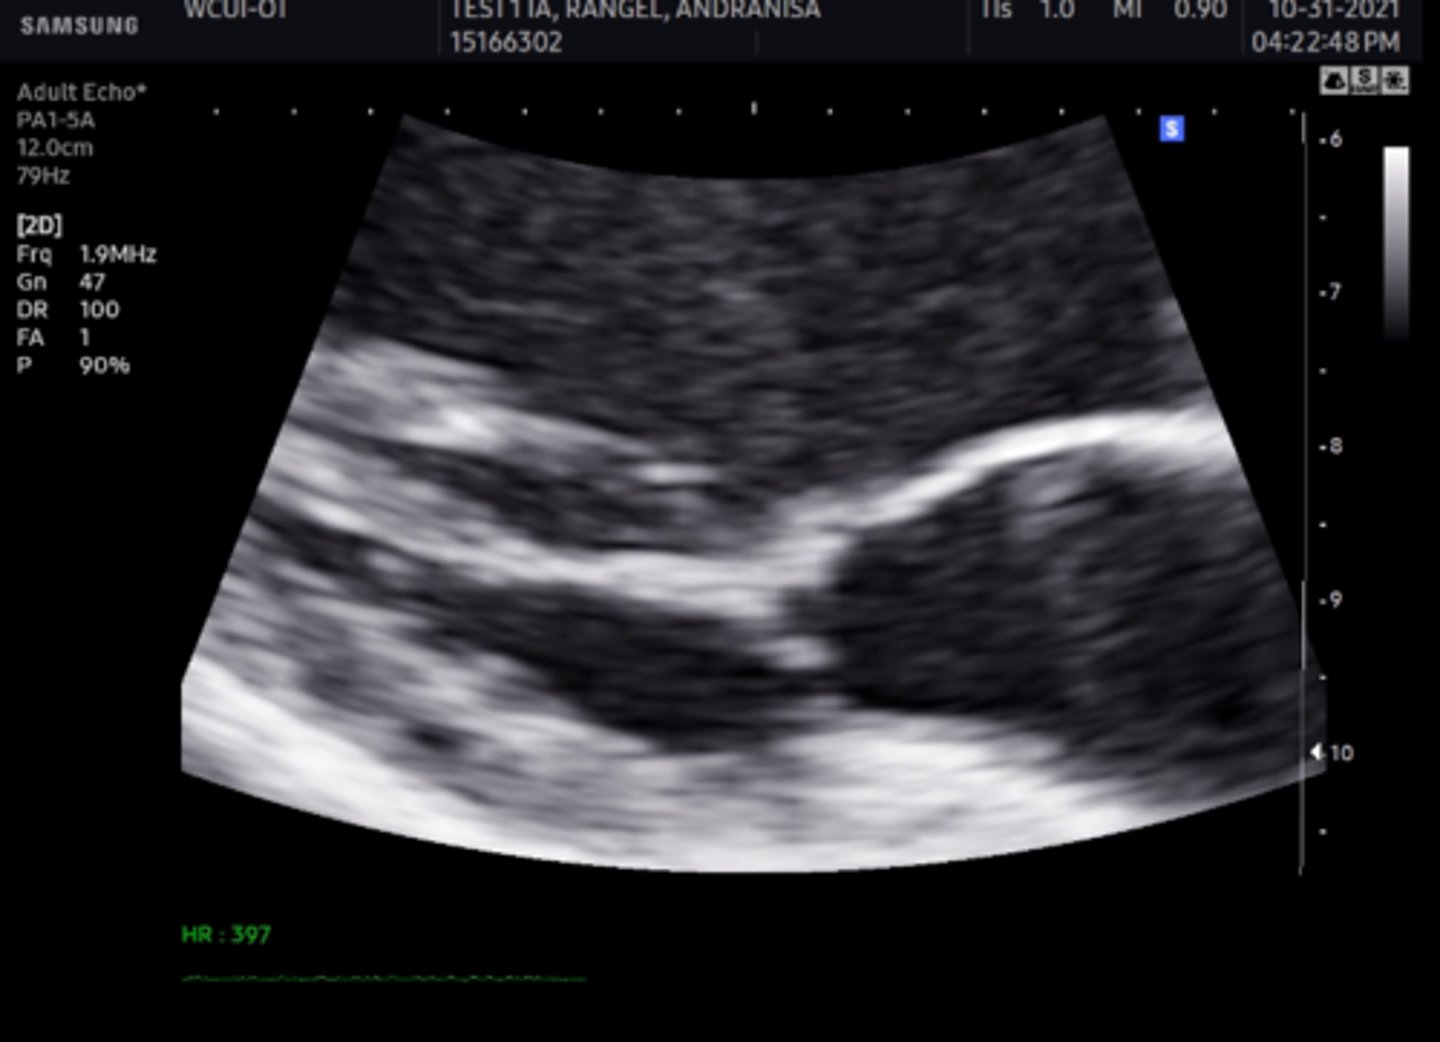

MV PLAX (top leaflet)

AMVL

MV PLAX (bottom leaflet)

PMVL